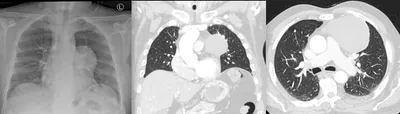

Mesenteric lymphadenitis

CTAbdomenCoronal+1